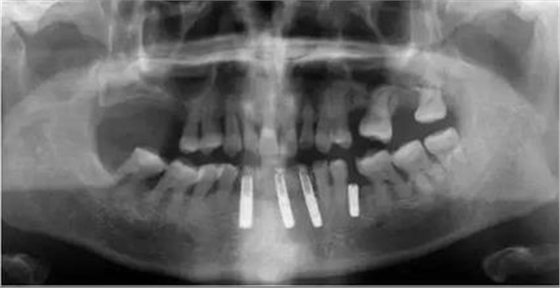

拔牙前CT截圖

▲女性,42歲,牙周病,下前牙固定不良修復(fù)體,基牙炎癥、松動(dòng)。

▲下前牙數(shù)字化導(dǎo)板引導(dǎo)下種植后即刻修復(fù),6顆缺失牙,擬種植3-4顆